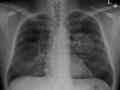

शरीर कई प्रकार कि कोशिकाओं से बना है। यह कोशिकाएं शरीर में बदलावों के कारण बढ़ती रहती हैं। जब ये कोशिकाएं अनियंत्रित तौर पर बढ़ती हैं और पूरे शरीर में फैल जाती हैं, तब यह शरीर के बाकि हिस्सों को अपना काम करने में दिक्कत देती हैं। जिससे उन हिस्सों पर कोशिकाओं का गुच्छा सौम्य गांठ या ट्यूमर बन जाता है। इस अवस्था को कैंसर कहते हैं। यही ट्यूमर घातक होता है और बढ़ता रहता है। कैंसर के विभिन्‍न प्रकार, सर्वाइकल कैंसर, ब्‍लैडर कैंसर, कोलोरेक्‍टल कैंसर, स्‍तन कैंसर, ब्रेन ट्यूमर, एसोफैगल कैंसर, पैंक्रियाटिक कैंसर, बोन कैंसर हैं।